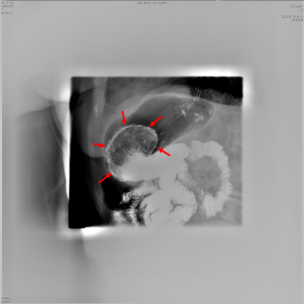

因患者高龄,既往冠心病史多年,有一过性晕厥病史,胃镜诊治危险性高。患者口服PPI及碳酸氢钠,联合口服碳酸饮料治疗溶石,7日后,行胃超声检查评估目前胃石情况。超声所见如下:

3,4  胃腔内见结石强回声,后伴明显声影,长约7cm